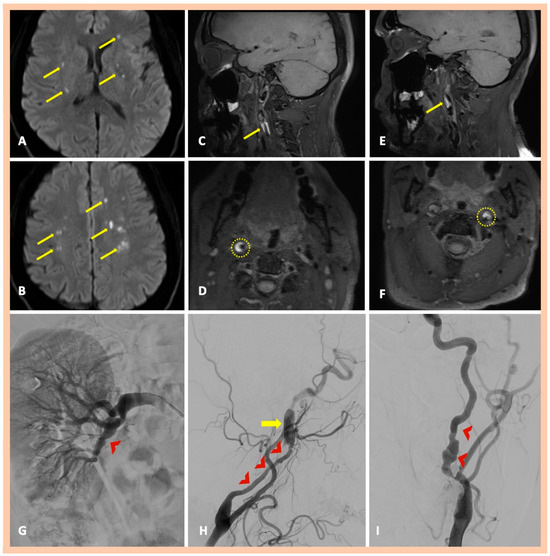

| Pat. #7 | Yes—multiple ischemic lesions in different arterial territories | Stenoses along the cervical segments of the right and left ICA. Characteristic “string-of-beads” appearance along the cervical segment of the left ICA | Intramural hematoma along the cervical segment of the right ICA. Intramural hematoma along the cervical segment of the left ICA, combined with the typical beaded appearance | DSA confirmed the findings and also revealed a focal stenosis of the right renal artery | Asymptomatic right and symptomatic left ICA dissections | 2 | Yes—focal stenosis of right renal artery |